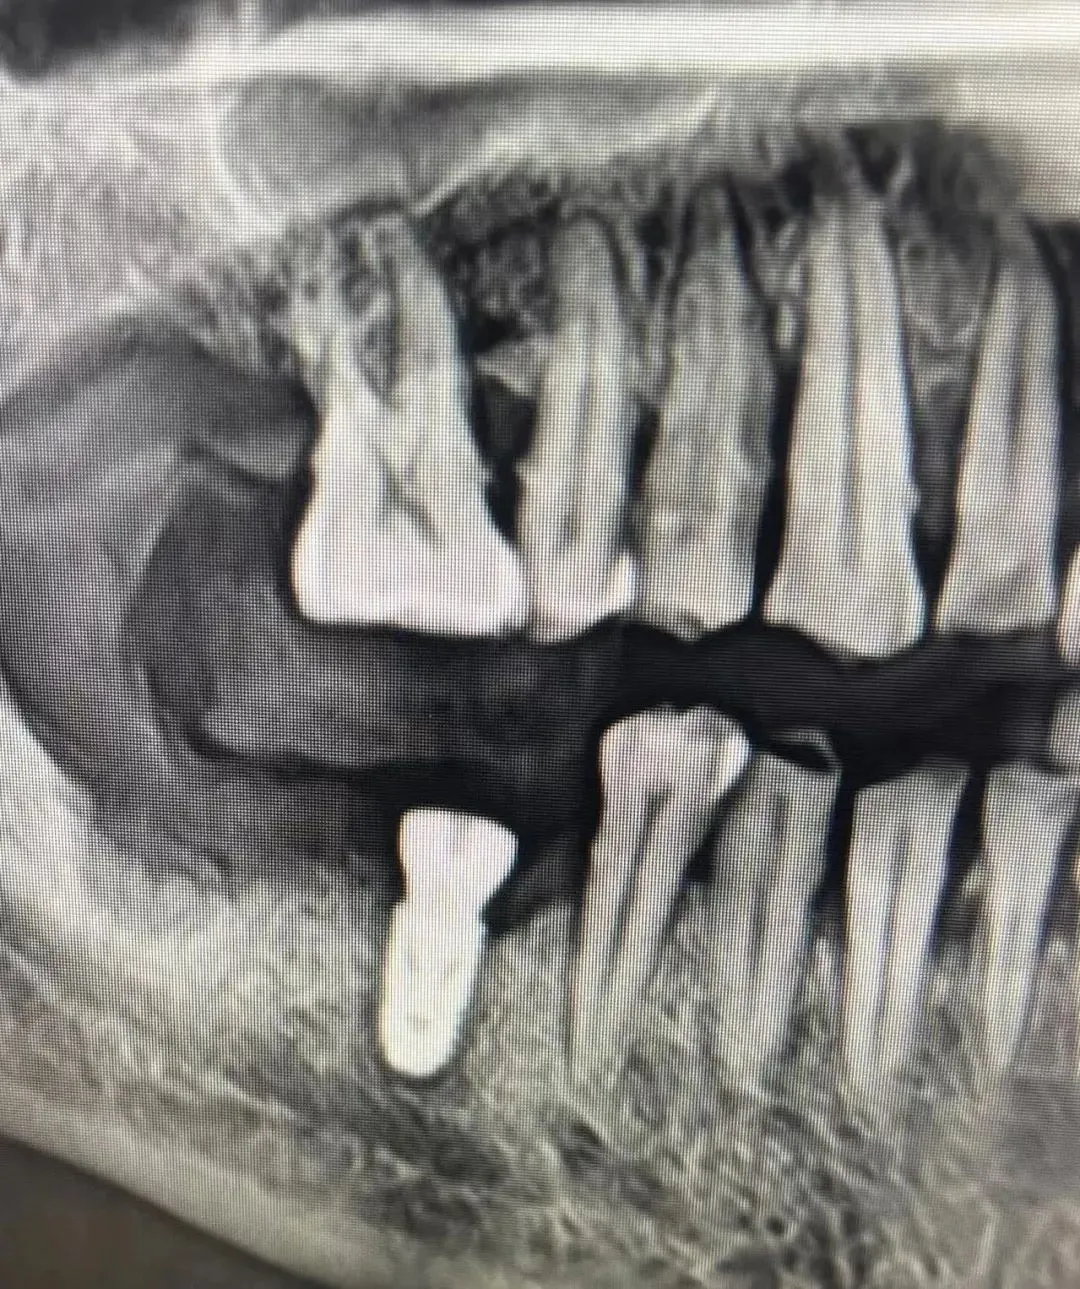

7、种植影像学分析;可以获得骨高度 ,骨宽度信息 ,甚至可以模拟种植体植入位点

11、精准种植;单颗前、后牙的理想植入位点

六、学员回家后部分病例